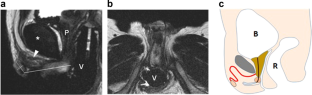

Assigned female at birth with anorgasmia possess a smaller clitoral glans and clitoral components farther from the vagina lumen than women with normal orgasmic function. There are no studies evaluating this correlation in operated transgender women. We evaluated whether differences in MRI measurements of neoclitoris volume and distance between the neoclitoris and the neovagina were correlated with differences in sexual function. We recruited for a prospective survey study 40 operated male to female patients (oMtF) who had undergone genital gender affirming surgery and postoperative pelvic MRI. Individual pelvic MRIs were reviewed by two blinded investigators, the three axes of the neoclitoris were measured and the volume was calculated using the ellipsoid formula. The distance between the neoclitoris and the neovagina was also measured. Sexual functioning was assessed using the Female Sexual Function Index (FSFI) and the operated Male to Female Sexual Function Index (oMtFSFI). Mean scores differences in FSFI, oMtFSFI were examined; associations with clitoral size, location, sexual functioning and demographical variables were investigated as well. The response rate was 55%, 11 MtFs operated with pubic neoclitoris technique (PNT) and 11 with neo-urethroclitoroplasty according to Petrović (NCP). The NCP group presented a neoclitoris mean volume of 1.04 (SD 0.39) cc vs 1.31 (SD 0.78) cc of the other group (p = 0.55). The mean distance between neoclitoris and neovagina was 4.20 (SD 0.57) cm in the PNT group and 2.55 (SD 0.45) in the NCP group (p < 0.001). Patients who had undergone NCP achieved a higher FSFI and oMtFSFI mean Total Score than those operated with the previous technique (FSFI 25.81 SD 3.02 vs 18.62 SD 9.92 p = 0.08; oMtFSFI 37.63 SD 8.28 vs 43.36 SD 13.02 p = 0.23). According to pelvic MRI measurements, this study suggests a correlation between neoclitoral location and oMtF sexual satisfaction.

Vedovo, F., Pavan, N., Bertolotto, M. et al. Neoclitoral location may affect sexual function in transgender women: a preliminary pelvic MRI study. Int J Impot Res 36, 526–530 (2024). https://doi.org/10.1038/s41443-023-00716-2